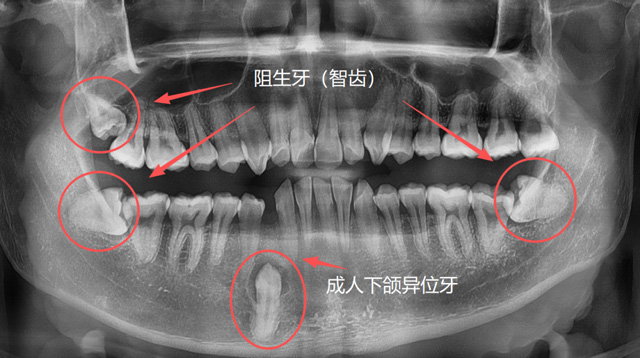

成人异位牙、阻生牙(智齿)

有些人因为牙列拥挤、乳牙滞留或先天发育等原因,恒牙没有在正常的位置萌出,反而往上颌窦、鼻腔等方向生长;称为“异位牙”,还有的牙因为全部或部分埋在了牙槽骨里,无法萌出,称为“阻生牙”,很多智齿就是这样的情况;还有一些超出正常数量的“多生牙”,通常也埋在牙槽骨里无法萌出。

大家可能要问了,如果长了这样的异常牙齿,都需要拔掉吗?答案是不一定。针对它们的处理方式如下:

部分异位牙可以通过正畸治疗牵引到正常位置。

多生牙、异位牙在没有产生不良影响的前提下,可保持现状。

影响到邻牙健康,反复发炎或者形成了囊肿的牙,需要及时拔除。

长在上颌窦、鼻腔方向的异位牙,长在牙槽骨深处的多生牙,常常埋伏于骨内,需要骨开窗才能拔除,具有一定的难度。